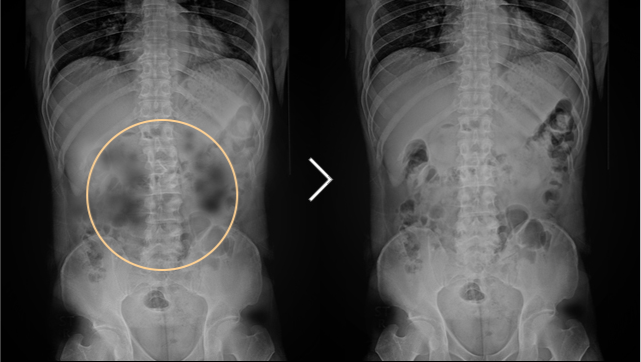

• 척추측만증 치료 전후사진

척추측만증 3개월 감압 치료 후

경부동통 및 상지 방사통 사라짐